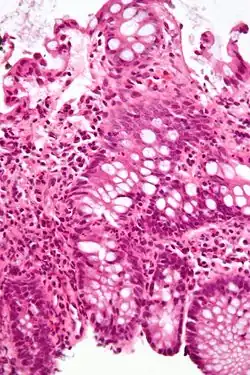

| Micrograph showing inflammation of the large bowel in a case of inflammatory bowel disease. Colonic biopsy. H&E stain. | |

The diagnosis is usually confirmed by biopsies on colonoscopy. Fecal calprotectin is useful as an initial investigation, which may suggest the possibility of IBD, as this test is sensitive but not specific for IBD.[55][56]